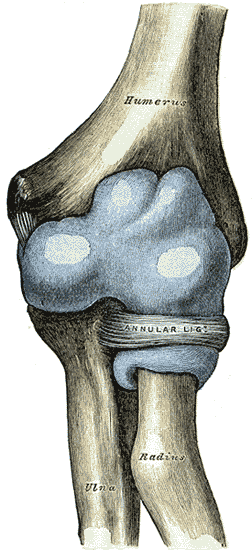

The elbow joint has three different portions surrounded by a common joint capsule. These are joints between the three bones of the elbow, the humerus of the upper arm, and the radius and the ulna of the forearm.

Joint capsule

The elbow joint and the superior radioulnar joint are enclosed by a single fibrous capsule. The capsule is strengthened by ligaments at the sides but relatively weak in front and behind.[7]

Left: anterior and ulnar collateral ligaments

Right: posterior and radial collateral ligaments

The elbow, like other joints, has ligaments on either side. These are triangular bands which blend with the joint capsule. They are positioned so that they always lie across the transverse joint axis and are, therefore, always relatively tense and impose strict limitations on abduction, adduction, and axial rotation at the elbow.[7]